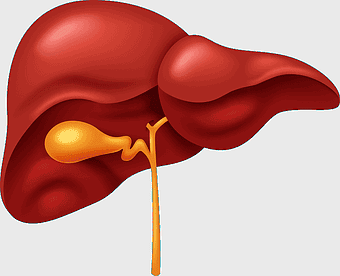

- kidney and liver diagram

human digestive system, gastrointestinal tract anatomy, liver function, stomach and intestines, digestive health, internal organs diagram, human body systems -

human liver anatomy, medical imaging liver, liver radiology scan, human digestive system liver, abdominal organ visualization, internal anatomy illustration, liver health diagram -

liver illustration, human liver cartoon, cartoon liver image, liver organ diagram, liver anatomy visual, medical liver graphic, liver health depiction -

liver with gallbladder diagram, human liver function, bile production organ illustration, digestive system anatomy, liver and bile duct visual, human anatomy medical graphic, hepatology reference image -

human liver model, liver organ cirrhosis drawing, medical anatomy illustration, red liver organ, bile duct structure, hepatic lobe depiction, digestive system organ -

human liver anatomy, liver function tests, hepatocyte function, fatty liver disease, liver organ diagram, medical liver illustration, human body organ study -